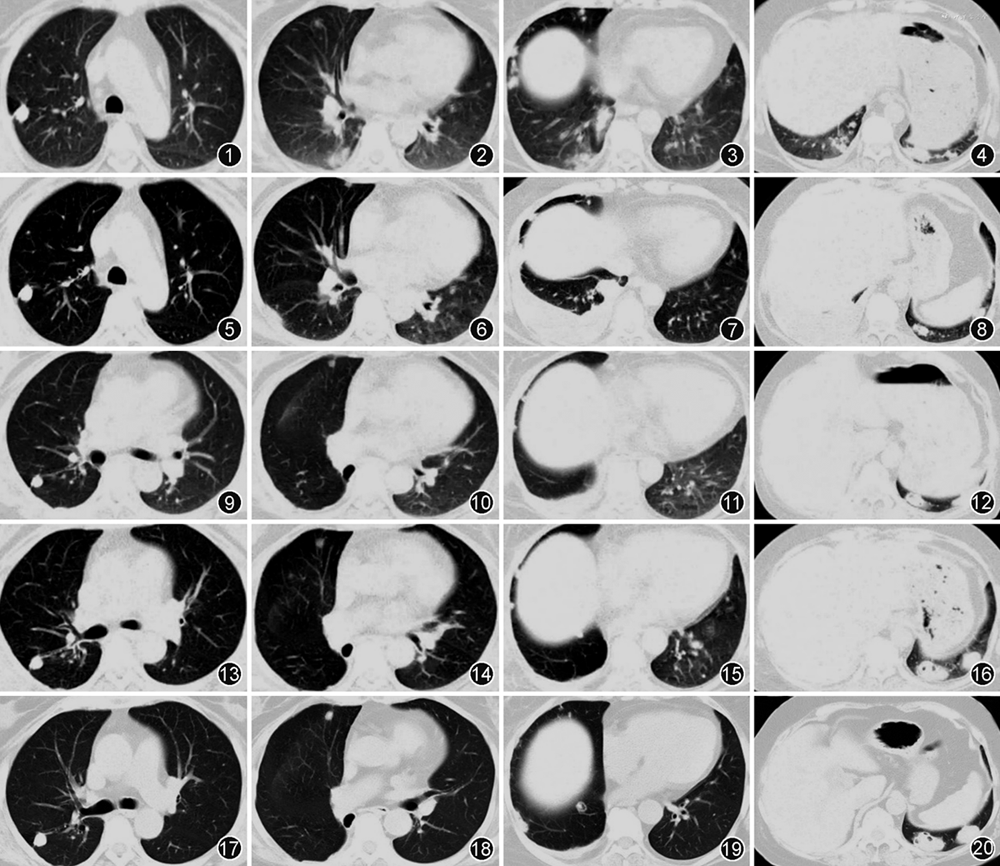

患者女,64岁,主因“右侧胸痛4年余,左侧胸痛9个月余”于2023年2月21日入院。2018年10月患者因“免疫性血小板减少性紫癜”行CD20单抗治疗后出现右侧胸痛,以针刺样疼痛为主,季肋部为著,深呼吸时加重。伴有间断发热,最高体温39 ℃,伴有寒战,以夜间为著。伴有咳嗽、咳黄痰,痰量多,黏稠不易咳出。无咯血、盗汗、呼吸困难等不适。于外院给予头孢类抗生素(具体不详)治疗1周后,咳痰、发热明显好转,右侧胸痛未见改善。胸部CT(图1~4)示双肺多发结节。2019年1月因右侧胸痛加重就诊于解放军总医院海南分院,气管镜下未见异常,PET-CT考虑非肿瘤性病变,行CT引导下经皮肺穿刺活检,病理未见肿瘤征象,未予特殊治疗。2019年3月就诊于佳木斯当地医院,考虑肺结核可能性大,给予规范四联(异烟肼、利福平、乙胺丁醇、吡嗪酰胺)抗结核药物治疗。2019年5月患者右侧胸痛症状加重,胸部CT(图5~8)示双肺多发不规则结节影,右侧胸腔积液。行右侧胸腔穿刺,引出血性胸腔积液,性质为渗出液,胸腔积液常规检查可见多个核细胞占比81.9%,腺苷脱氨酶(ADA)44.54 U/L,葡萄糖1.25 mmol/L,仍考虑结核可能性大,继续抗结核药物治疗。2019年12月患者突感右侧胸痛加剧,呼吸困难,胸部CT示右侧局限性液气胸,于北京市胸科医院行右肺下叶切除+部分胸膜剥脱+黏连松解术,术后右肺下叶标本病理示肉芽肿性炎伴坏死,分枝杆菌分子基因检测阴性。手术后右侧胸痛症状较前缓解,继续抗结核药物治疗2个月后自行停用,2020年5月复查胸部CT(图9~12)示右肺下叶切除术后,双肺多发结节,部分结节增大,结节内形成空洞。

2022年5月患者无明显诱因出现左侧胸痛,以针刺样疼痛为主,季肋部为著,深呼吸时加重,无发热、咳嗽、咯血、盗汗、体重下降等,给予莫西沙星口服3周未见缓解,胸部CT(图13~16)示双肺多发结节,左下肺结节较前增大伴有空洞形成。2023年1月就诊于解放军总医院海南分院,考虑不除外隐球菌肺炎,给予氟康唑口服(450 mg/次,1次/d),治疗3周,患者自觉左侧胸痛症状较前好转。2023年3月,为行进一步诊治,就诊于首都医科大学附属北京朝阳医院,行胸部CT示双肺多发结节,较前增大、增多(图17~20),病程中患者偶有手关节不适,近3个月踝关节肿痛,右足麻木。

石欣雨(呼吸与危重症医学科):本例特点:(1)老年女性,慢性病程。(2)既往类风湿关节炎、2型糖尿病及免疫性血小板减少性紫癜病史。(3)主要症状为胸痛,不伴其他系统症状。右侧胸痛4年余,手术切除右下叶后右侧胸痛缓解,左侧胸痛9个月余,病程中先后给予头孢类抗生素及莫西沙星抗炎、四联抗结核等药物治疗,双肺多发结节病变仍持续进展。应用氟康唑治疗后患者自觉症状较前略减轻。(4)5年前起秋冬季居住在海南,居住环境潮湿。(5)体检:双侧胸廓对称,双肺呼吸音粗,右肺呼吸音减弱,双肺未及明显干湿性啰音,未闻及胸膜摩擦音。(6)实验室检查:类风湿因子 125 U/ml,抗CCP抗体2 006.61 U/ml,结核、隐球菌、血管炎、肿瘤等实验室检查指标均阴性。(7)胸部CT示双肺多发结节影,多位于胸膜下,边缘清晰,结节周围肺组织、气管形态、血管纹理均无异常。部分结节伴空洞形成,抗结核治疗无效,右肺上叶胸膜下的结节变化不大,余双肺多发结节增大且数量增多,部分形成空洞,逐步进展。(8)右肺下叶切除病理示肉芽肿性炎伴坏死。

高燕莉(放射科):本例患者胸部影像学表现为胸膜下分布的双肺多发结节伴空洞形成。其中右肺上叶结节多次复查胸部CT未见明显变化,考虑为陈旧性结核。其余结节的形态、分布及演变过程与肺类风湿结节的文献报道相符。肺类风湿结节主要表现为:单发或多发,边界多光滑,大小从几毫米到几厘米不等,实性、部分实性或伴有空洞形成的多位于胸膜下或小叶间隔的结节[10, 11, 12, 13]。影像学上需与包括结核、真菌感染在内的感染性疾病及血管炎等疾病相鉴别。首先是肺结核,其结节好发在双肺上叶尖后段及下叶背段。影像学表现多样,可表现为实变影、空洞和结节影。病变的分布多沿气道分布,周围可见卫星灶、树芽征。本例患者双肺多发结节逐渐增大并伴有空洞形成,病变无气道分布特征,周围也未见卫星灶及树芽征,影像不符合典型肺结核的表现。其次是肺隐球菌病,多分布在肺野外带或胸膜下区域,下叶多见。可表现为单个或多个胸膜下孤立结节或多发结节伴肿块,结节或肿块部分可成融合趋势,边界多较清楚。也可表现为大片的斑片实变影或弥漫粟粒影。本例患者的影像表现以胸膜下结节为主的多发的伴有空洞形成的结节,影像上不能除外隐球菌肺炎。最后是GPA,其影像学常见特征为:多发性、多形性、多变性,典型征象为弥漫性分布的多发结节或肿块合并空洞,结节大小不一,几毫米至数十厘米不等,50%的结节呈空泡状,多见于>2 cm的结节,部分的结节可能有“晕征”,提示邻近的实质性出血[14]。空洞常有增厚的壁,其特征是内边缘不规则和无钙化[15]。本例患者胸膜下分布,病变无血管分布特征,且周围没有晕征,影像上不符合典型的血管炎表现。综上所述,肺类风湿结节的影像学表现无明显特异性,与隐球菌、肉芽肿性多血管炎等疾病的影像表现类似,临床上需要结合临床表现、实验室检查、影像学及病理结果综合判断。

随诊:明确诊断后,患者出院。院外患者口服醋酸泼尼松(50 mg,1次/d)和吗替麦考酚酯(0.75 g,2次/d),2周后醋酸泼尼松减至45 mg,1个月后患者胸痛症状缓解,复查胸部CT(图24~27)可见左下肺最大结节长径由4.2 cm缩小至3.4 cm。醋酸泼尼松继续减量,2周减1片。